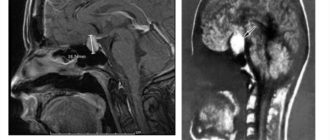

Признаки, лечение, последствия микроаденомы гипофиза головного мозга Микроаденома, появившаяся в переднем отделе гипофиза –

Беременность при микроаденоме гипофиза: можно ли забеременеть и рожать при заболевании Микроаденомой гипофиза называется

Показатели пролактина при аденоме гипофиза Повышение уровня пролактина в крови при аденоме гипофиза приводит